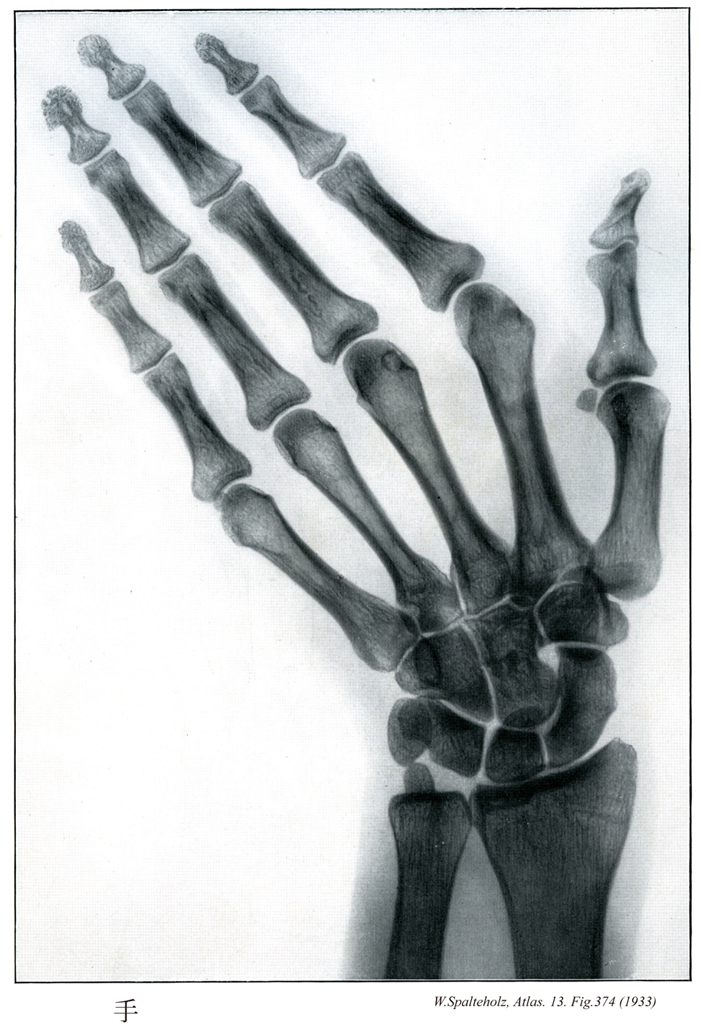

374

【Hand

手;テ

Manus】

→(手は上肢のうち橈骨手根関節より遠位の部分。手根と中手に区別され、手根と中手の前面を手掌、後面を手背という。皮膚節において第六頚神経、第七頚神経、第八頚神経のレベル。)